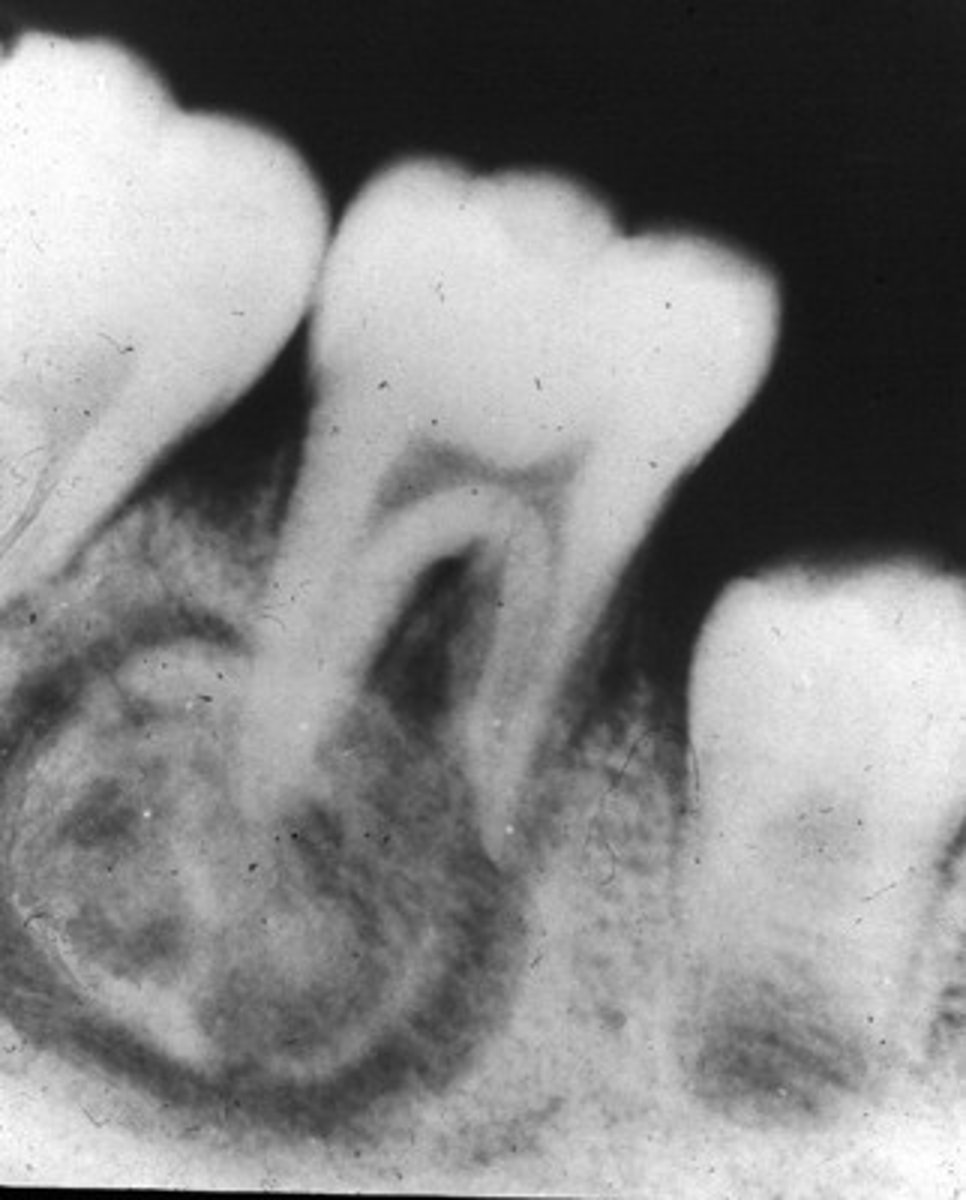

Periapical Cemental Dysplasia

localized change of normal cancellous bone with fibrous tissue and cementum-like material

Location of Periapical Cemental Dysplasia

Apex, mandibular anterior teeth

Periphery of Periapical Cemental Dysplasia

well defined,RL border

Internal structure of Periapical Cemental Dysplasia

early stage (apical RL), mixed stage, mature